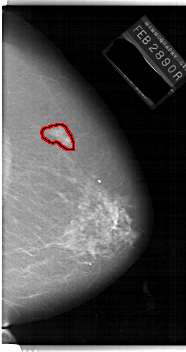

A_1144_1.RIGHT_MLO

RIGHT_MLO LINES 6721 PIXELS_PER_LINE 3301 BITS_PER_PIXEL 12 RESOLUTION 43.5 OVERLAY

FILE: A_1144_1.RIGHT_MLO.OVERLAY

TOTAL_ABNORMALITIES 1

ABNORMALITY 1

LESION_TYPE MASS SHAPE IRREGULAR MARGINS ILL_DEFINED

ASSESSMENT 4

SUBTLETY 4

PATHOLOGY MALIGNANT

TOTAL_OUTLINES 1

BOUNDARY